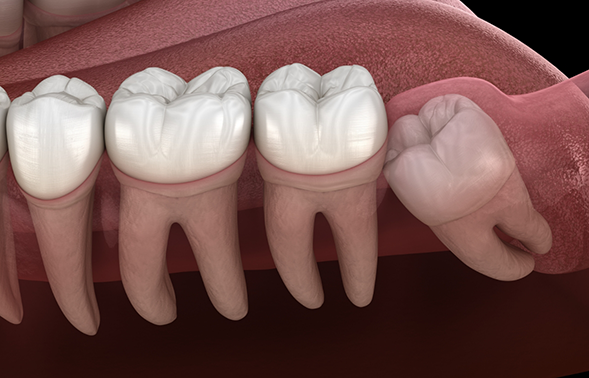

Impacted Wisdom Teeth

It’s relatively common for the wisdom teeth to become stuck while trying to come in, or impacted. In addition to causing pain in the back of the jaw, impacted wisdom teeth can also create a flap in the gum line that easily traps plaque and food particles, dramatically increasing a person’s risk for developing cavities. They often require a surgical extraction in order to be removed, and thankfully, our team has performed this kind of procedure countless times before.